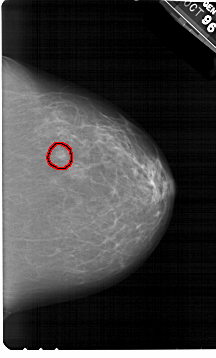

A_1381_1.RIGHT_CC

FILE: A_1381_1.RIGHT_CC.OVERLAY

TOTAL_ABNORMALITIES 1

ABNORMALITY 1

LESION_TYPE MASS SHAPE OVAL MARGINS ILL_DEFINED

ASSESSMENT 4

SUBTLETY 3

PATHOLOGY BENIGN

TOTAL_OUTLINES 1

BOUNDARY